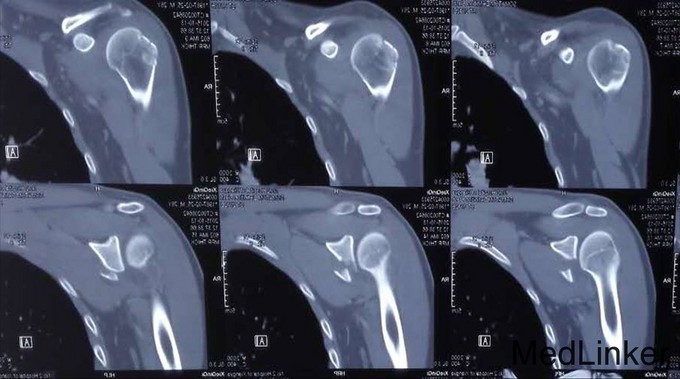

患者谢某某,男性,28岁,已婚 患者坠马后摔伤右肩部,局部肿痛伴活动受限7日 外院就诊摄片示:右肩胛骨折;右肱骨大结节骨折 右上肢外展支架外固定

右肩甲盂骨折

右侧臂丛神经阻滞麻醉 右肩关节前路切开复位螺钉内固定术 术后12日右上肢悬吊固定